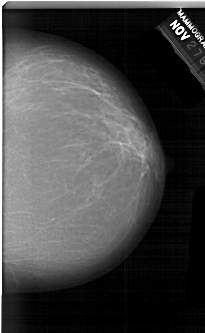

A_1519_1.LEFT_MLO

LEFT_MLO LINES 6871 PIXELS_PER_LINE 4276 BITS_PER_PIXEL 12 RESOLUTION 43.5 OVERLAY